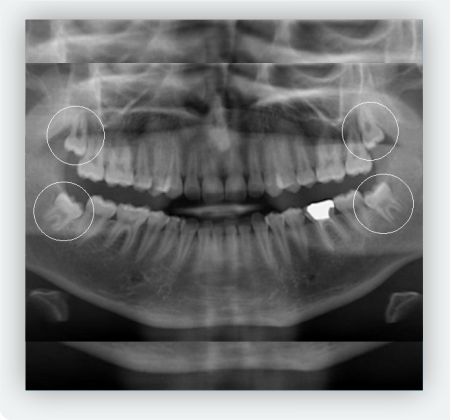

Lo primero que debes hacer es agendar una cita de valoración con nuestro especialista en cirugia oral y maxilofacial; el Dr. Felipe Naranjo, el realizará una valoración clínica de tu caso, y con la ayuda de radiografias realizará la extracción de las piezas en caso tal que sea necesario. La extracción de muelas cordales es un procedimiento seguro, realizado bajo anestesia local, con técnicas modernas que minimizan el dolor y aceleran la recuperación.

Un diagnóstico adecuado es clave para decidir si se deben extraer o no. En Clínica Ártica contamos con especialistas en cirugía oral y tecnología avanzada para evaluar tu caso de manera precisa.